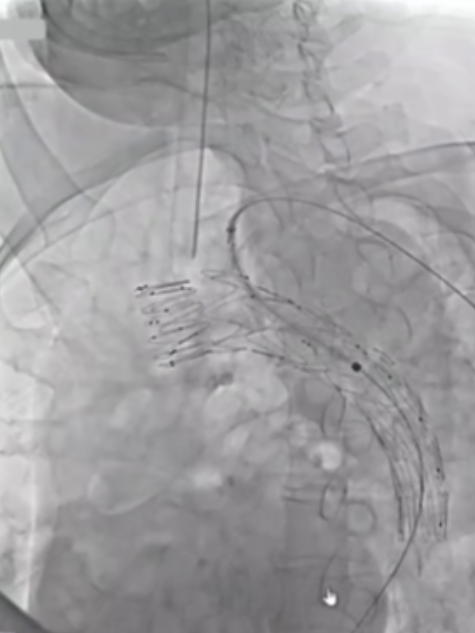

香港玛丽医院分享了38例主动脉弓分支支架植入病例的经验,其中28例为A/Br型,8例为B/Br型,1例为L型,患者平均年龄75.5岁,男性34例。30天死亡率为7.8%,手术中风率10.5%(2例严重+2例轻微),再干预率21%,逆行夹层3例,动脉瘤相关死亡2例。

此外,报告强调了健康主动脉的重要性,升主动脉直径<38mm是关键标准。曾有案例显示,在40mm主动脉植入支架后发生灾难性逆行A型夹层,这警示临床医生必须在健康主动脉段锚定,避免在夹层病理区域进行操作。

在主动脉介入治疗领域,支架设计持续创新。Terumo双分支支架采用大型矩形凹槽设计,即便旋转90度,仍能顺利接入分支,对于弓部曲线较为紧张的情况适配性更强。不过,该支架也面临技术挑战,手术中需要精准控制支架的旋转与对齐,以确保治疗效果。

深圳设计的支架同样亮点十足。它具有短输送尖端的特点,无需跨越主动脉瓣,部署过程简单,且不需要进行严格的血压控制。支架配备两个平行侧支,搭配低剖面8-9F桥接支架,在接入方式上,采用右臂入路结合左颈动脉小切口的方式,为手术操作提供了便利,也有望为患者带来更优的治疗体验。